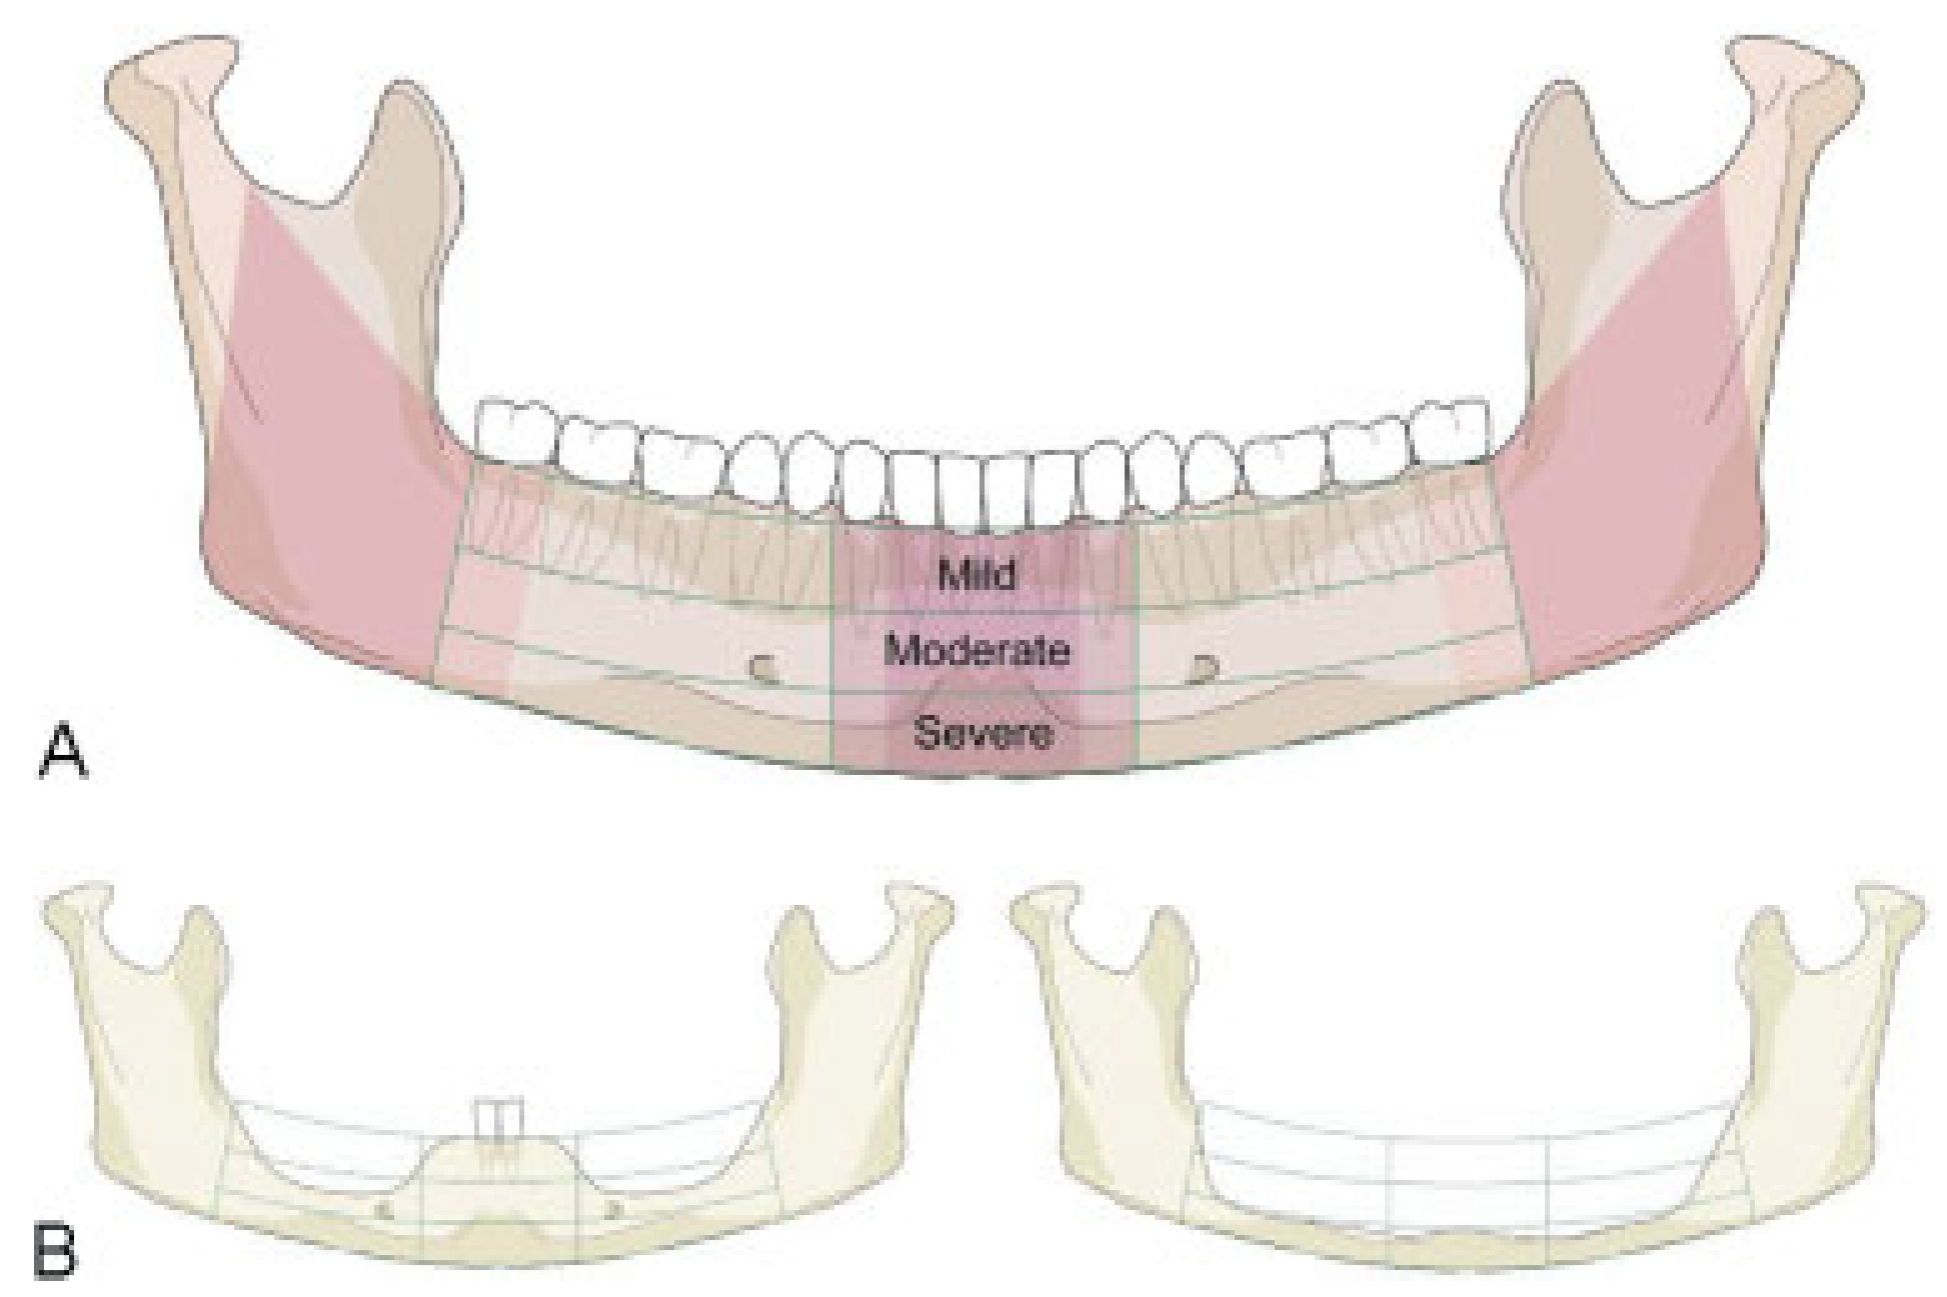

The degree of vertical atrophy is specified separately for the body regions (left and right) and the symphysis (Figure 3). In the partially edentulous mandible the bony atrophy principally can take the same form as in complete edentulism, though commonly the vertical atrophy is not as accentuated adjacent to remaining teeth or in tooth gaps. Bony atrophy in partial edentulism is recorded checking the plausibility with the residual tooth pattern.

Figure 3.

Illustration of mandibular edentulism and atrophy. (A) "Atrophy grid" superimposed on a fully dentulous mandible with permanent teeth. The mandibular body regions, the para–symphsis and the transitional zones depicted as vertical sectors are maintained unchanged. To allocate the fractures to a topographical site the borderlines/frontiers of the region are transferred to the edentulous situation. (B) Left side: Moderate level of atrophy (code 2) on both the body regions, but no atrophy (code 0) in the parasymphysis. Right side: Severe level of atrophy (code 3) over the whole arch of the edentulous mandible ("pencil bone").